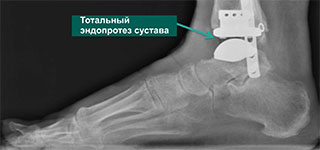

При неэффективности консервативного лечения, сильной деформации костных структур голеностопа, развившихся тяжелых осложнениях показано хирургическое вмешательство. Нередко применяется артродез, при котором сустав закрепляют в функционально выгодном положении. Пациенту также может быть предложено эндопротезирование — замена голеностопа имплантатом.